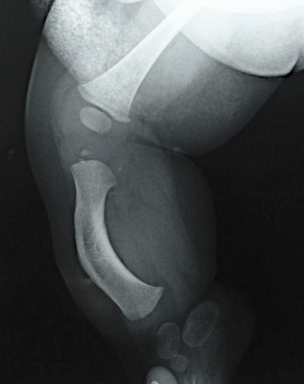

El tratamiento de la Pseudoartrosis Congénita de Tibia y Peroné (PCTyP) ha sido diverso. Todas las técnicas de tratamiento tienen una cuota de complicaciones, pero es la re-fractura y la falta de unión las principales consecuencias que se desean evitar. El objetivo de esta investigación se basa en analizar las técnicas quirúrgicas empleadas en nuestro centro y determinar los resultados. Se realizó un estudio retrospectivo, donde se estudiaron 11 pacientes con esta enfermedad con un seguimiento promedio de 4,73 años (DS±4,56). Todos los pacientes en quienes se utilizó la técnica de Charnley-Williams (CW) lograron la consolidación, la protección del clavo funcionó hasta que el extremo proximal de la tibia queda desprotegido al crecer el hueso y se produjeron angulaciones en esta zona, usualmente en la tibia proximal. Con el uso del clavo endomedular (EM) telescópico de Fassier-Duval (FD) se logra la protección de todo el hueso, inclusive durante el crecimiento. Se concluye que la técnica de CW es un buen método para la resolución de esta enfermedad y con el uso del clavo EM de FD se evita la refractura y se logra la unión permanente a medida que continúa el crecimiento del hueso. La discrepancia de los miembros inferiores es debida a la afectación de la tibia que compromete su crecimiento normal.